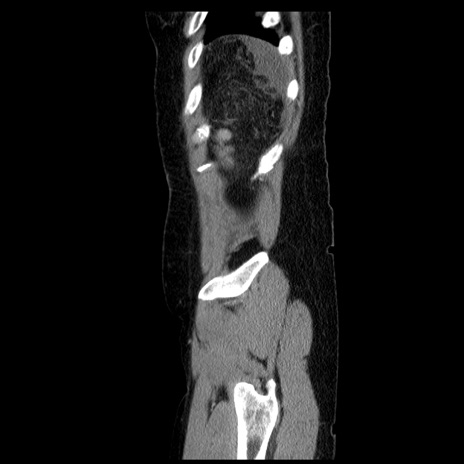

横断像